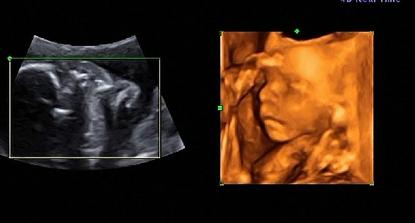

......bude to klučík.....